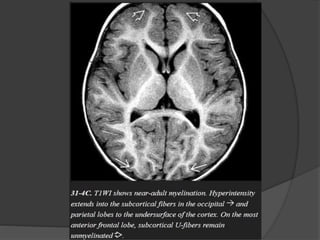

 Normal myelination… Hyperintense on T1 &

Hypointense on T2.

 T1W parallel increase in lipids while T2W

correlates to the period of maturation of myelin

sheath.

Three month

 Cerebellar folia.

 Ventral brainstem.

 Optic radiation.

 Anterior limb of internal capsule.

 Occipital subcortical U fibers.

 Corpus callosum splenium.

Six month

 Corpus callosum genu.

 Paracentral subcortical U fibers.

 Centrum semioval ( Partial ).

Eight month

 Centrum semiovale ( complete except

frontoteporal area ).

 Subcortical U fibers ( complete except most

rostral frontal area ).

Eighteen month

 Essentially like adult.